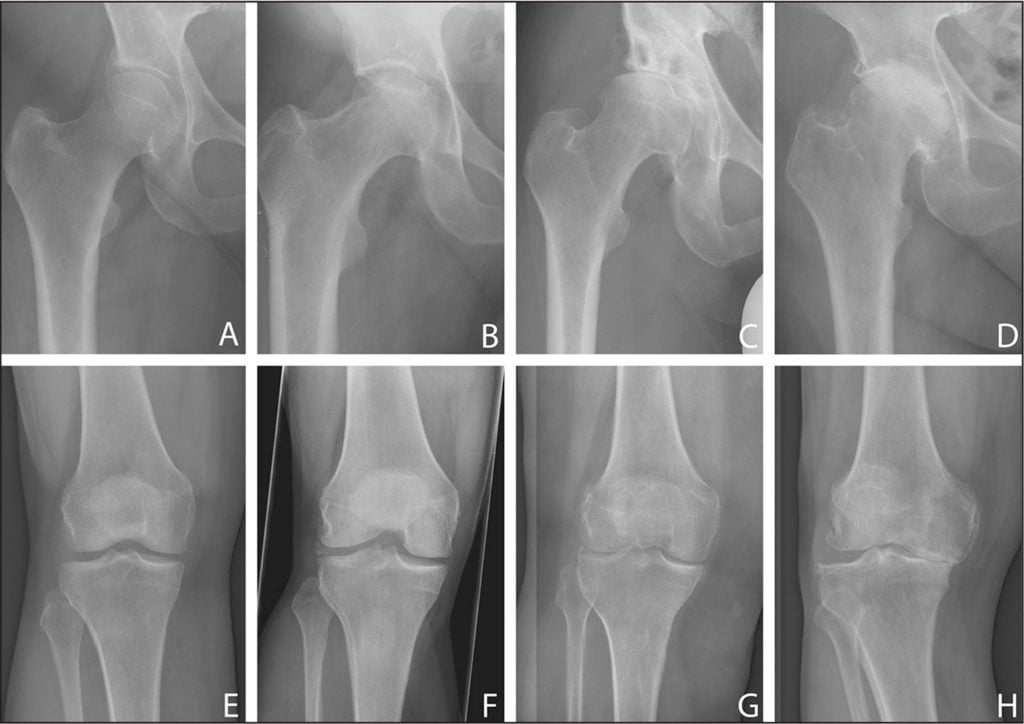

| Стадии деформирующего артрита | Клинические и рентгенологические проявления |

| Первая | В местах крепления связок формируются своеобразные заострения. В области коленей — межмыщелковые возвышения на участке крестообразных связок, в тазобедренных сочленениях — в области надмыщелков, боковых связок большеберцовых костей. Размеры суставных щелей не изменены. Болезненные ощущения возникают только при физических нагрузках. Если лечение начинается на этом этапе, то патология надежно купируется и дальше не развивается. О заболевании будут напоминать только окостеневшие участки в местах прикрепления связок |

| Вторая | Суставные щели сужены в результате изнашивания гиалиновых хрящей. Замыкательная пластинка склерозируется, уплотняется. Стадии ремиссии чередуются с рецидивами, возникающими все чаще. Объем движений в суставах существенно снижается, при сгибании или разгибании сустава слышится щелчки, хруст. Болезненные ощущения появляются даже в состоянии покоя, провоцируя бессонницу, быструю утомляемость. При диагностировании патологии используются консервативные методы лечения, редко дающий положительный результат |

| Третья | На рентгенологических изображениях заметно полное или частичное сращение суставных щелей и множество сформировавшихся крупных остеофитов около сочленений. Артралгия становится постоянной, усиливается при малейшем движении. Суставы тугоподвижны в течение всего дня из-за развившегося анкилоза. Консервативное лечение не эффективно, направлено только на устранение болей. Пациента готовят к хирургическому вмешательству — корригирующей остеотомии, но чаще к эндопротезированию |

Лечением деформирующего артрита занимаются ревматологи или ортопеды, постравматического — травматологи. Если в штате больницы таких специалистов нет, нужно записаться на прием к терапевту. Первичный диагноз выставляется на основании жалоб пациента, его внешнего осмотра, изучения анамнеза. Для подтверждения проводится ряд инструментальных и лабораторных исследований. Наиболее информативна рентгенография, позволяющая выявить все характерные признаки деформации суставов — субхондральный остеосклероз, сузившуюся щель, сформировавшиеся кисты и остеофиты.